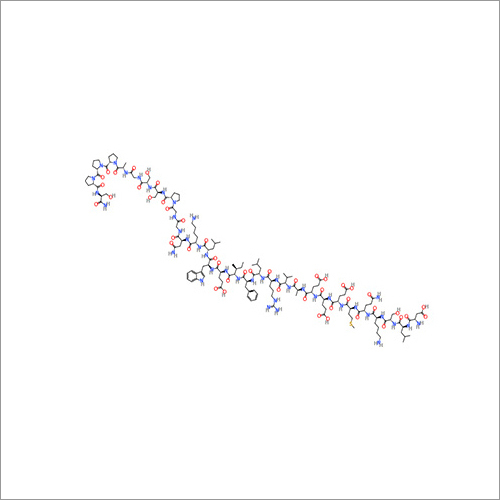

69558-55-0 थाइमोपेंटिन शुद्धता (%): > 99.0% (एचपीएलसी)

| रासायनिक नाम | Thymopentin |

| कैस नं | 69558-55-0 |

| रासायनिक नाम | Thymopentin |

| कैस नं | 69558-55-0 |